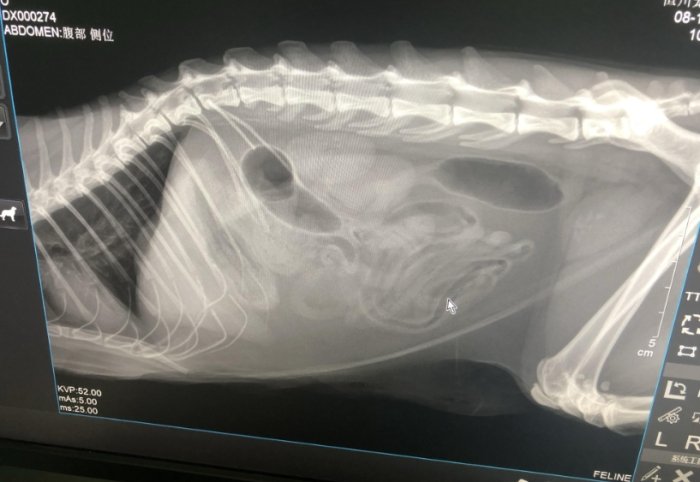

毛球症手術前,獸醫會做一堆檢查,比如X光或超音波,確認毛球的位置和大小。我帶咪咪去檢查時,獸醫還做了血檢,看貓咪能不能麻醉。這一步不能省,萬一貓咪有隱疾,手術風險會大增。